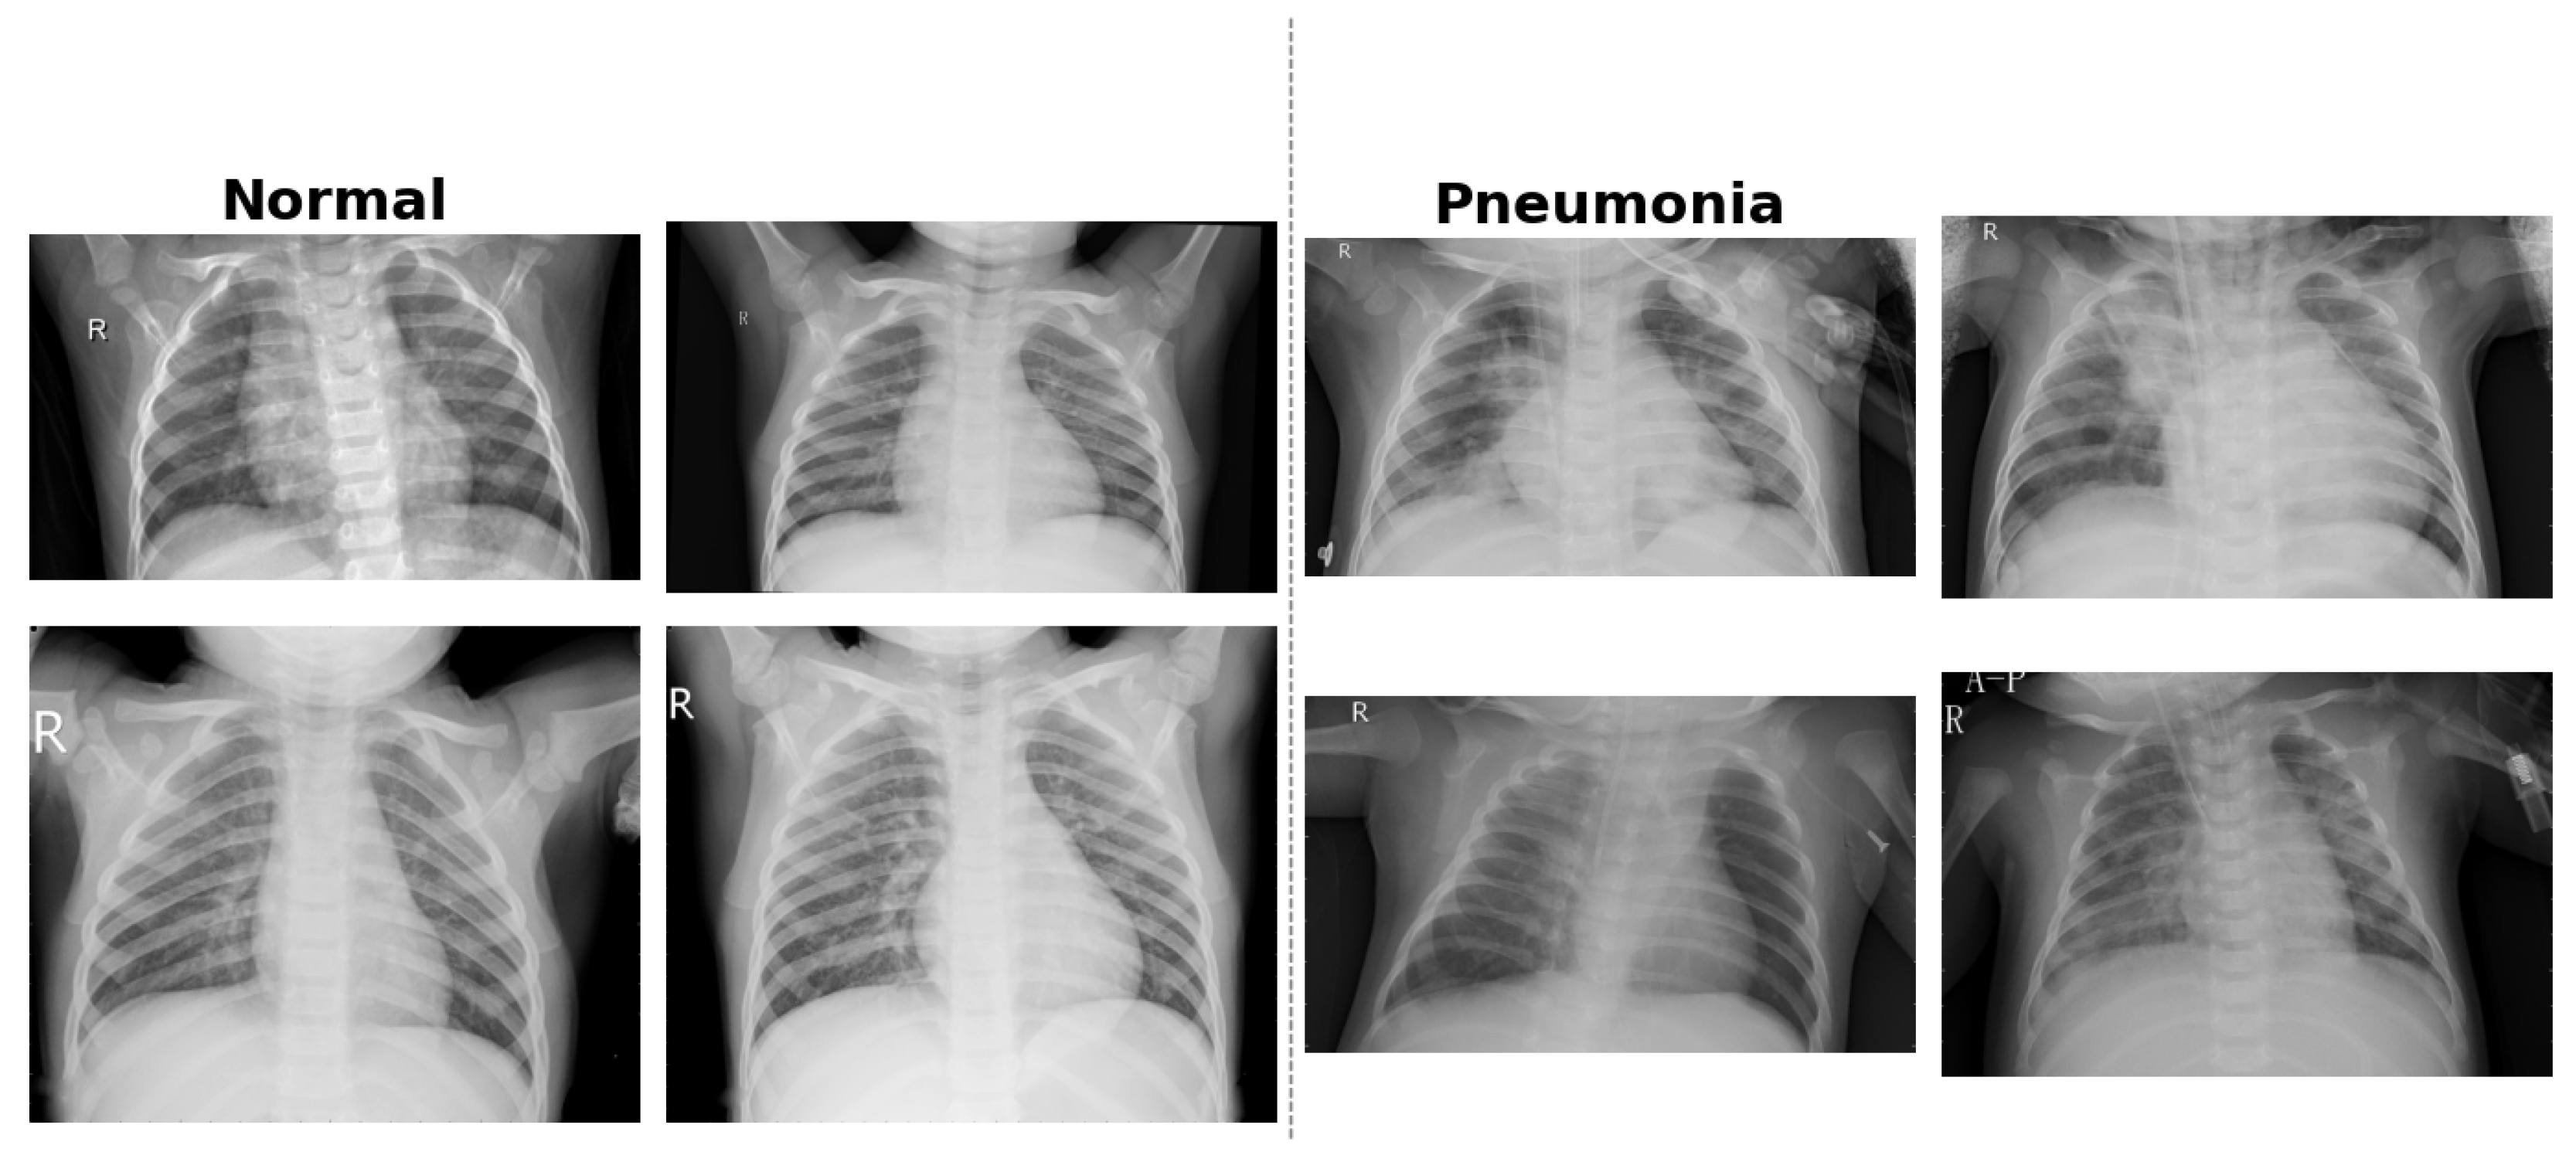

The dataset used in this study is the publicly available CXR Images (Pneumonia) dataset, which was originally introduced as part of a clinical study published in Cell journal [39]. It comprises 5,863 anterior-posterior (AP) CXR images of pediatric patients aged between one and five years. The data were collected at the Guangzhou Women and Children’s Medical Center in China as part of routine clinical care. All radiographs were initially screened for quality assurance, and low-quality or unreadable scans were excluded. Diagnostic labels—classified as either Normal or Pneumonia (bacterial or viral)—were assigned based on expert evaluation. Each image was graded independently by two certified radiologists, and to ensure diagnostic accuracy, a third specialist reviewed the evaluation subset to mitigate annotation errors.

The dataset is organized into three predefined folders: training, validation, and testing. These subsets are balanced across the two classes, facilitating supervised learning and consistent performance evaluation. The images are in JPEG format and exhibit sufficient resolution for feature extraction via CNNs. The dataset is available under a Creative Commons (CC BY 4.0) license and can be accessed through Mendeley Data [40]. Figure 4 provides example CXR scans illustrating the visual differences between normal lungs and those affected by bacterial and viral pneumonia.

Figure 4. Examples of pediatric CXR images: (left) normal lung, (middle) bacterial pneumonia with localized consolidation, and (right) viral pneumonia with bilateral interstitial patterns.